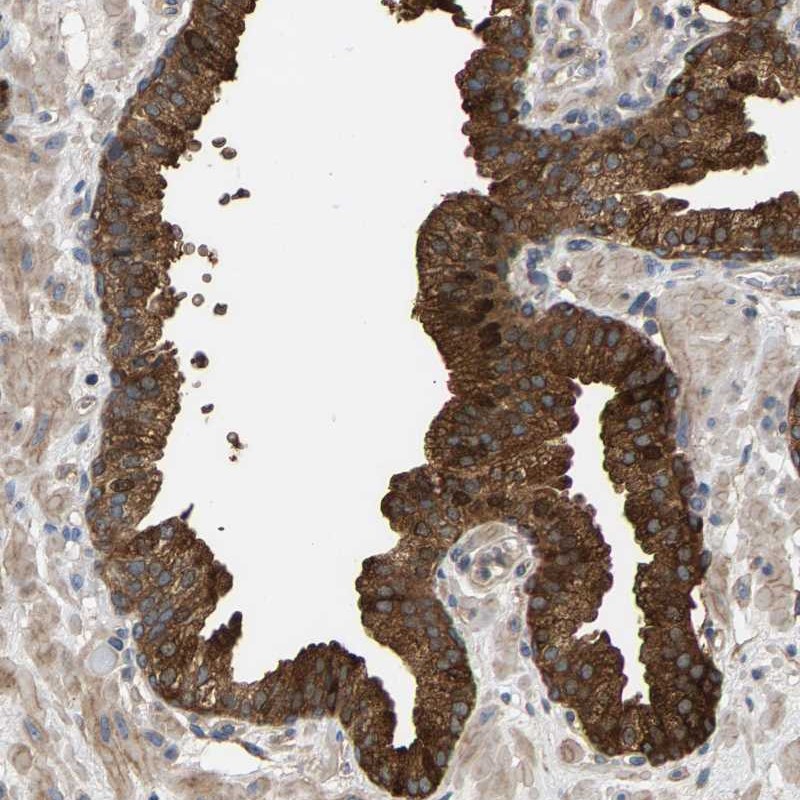

Immunohistochemical staining of human prostate shows strong cytoplasmic positivity in glandular cells.